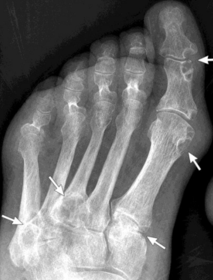

| What disease is this? What do the arrows indicate? | Gout Arrows = 'punched out' erosions |